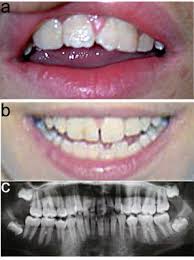

• Macrodoncia de los incisivos centrales superiores: Es el hallazgo más consistentemente observado. Puede haber otras anomalías en los dientes.

En la actualidad, el diagnóstico de síndrome de KBG se basa principalmente en los hallazgos clínicos y es confirmado con el examen genético que identifica la mutación en el gen ANKRD11. El diagnóstico final se logra generalmente después de la erupción de los incisivos centrales superiores permanentes a los 7 u 8 años de edad. Los criterios para el diagnóstico fueron definidos después de la revisión de 50 casos publicados en la literatura e incluyen [6][3] la presencia de los criterios principales (dismorfia facial, macrodoncia, anomalías esqueléticas y atraso en el desarrollo - comentados anteriormente) y alguna de las otras características que apoyan el diagnostico (baja estatura, anomalías en el EEG e implantación anormal del vello).

• Consulta con un ortodontista para evaluar la mal oclusión y la intervención.

[2] / Foto